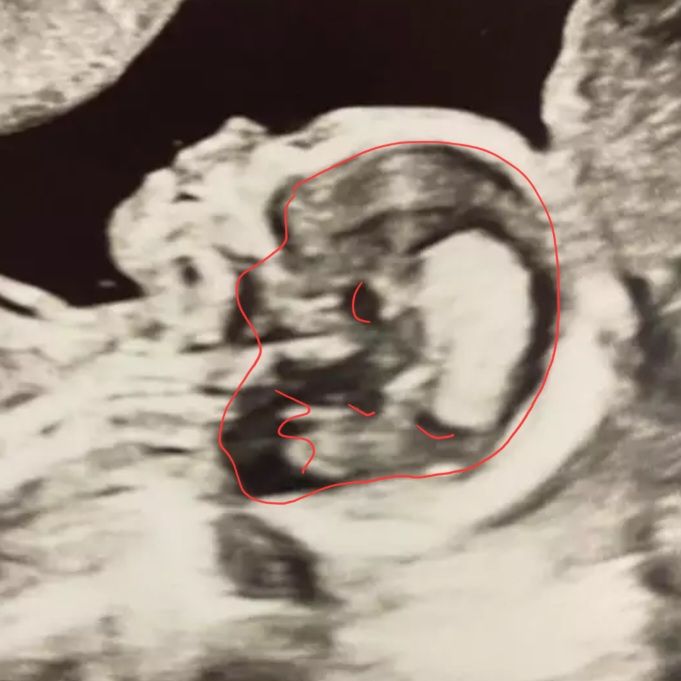

УЗИ 16 недель

УЗИ, КТГ, доплерДобрый вечер! Сегодня была контрольное УЗИ, идет 16я неделя. Все хорошо слава Богу, подарили на память фотку малыша 🤗

А чего ненормально? Это ж фотокадр. Губы поджал, разжал)), улыбнулся или наоборот. У меня есть кадр, где деть щеки надул и губы поджал. Отличная лялька

Это же УЗИ, там чего только не может получиться, особенно в нашей голове-фантазия

Happy mommy, они самые, просто фантазия играет 😀 нормальная перегородка между носом и губами, не волнуйтесь, скорее - так лежит ребёнок